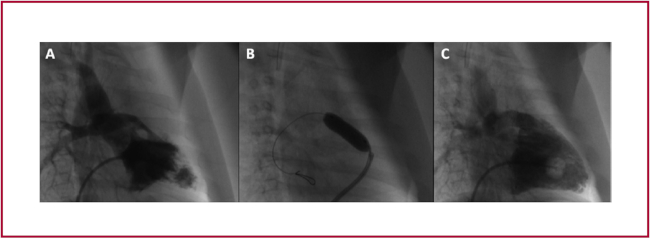

La angiografía ventricular derecha inicial se realizó a través de un catéter de diagnóstico tipo Berman angiográfico (Arrow®, USA) colocado en el ápex del ventrículo derecho en proyección oblicua anterior derecha 45°, y en proyección lateral izquierda estricta a 90°. Posteriormente, se realizaron sistemáticamente mediciones del tronco y las ramas de las arterias pulmonares, el anillo de la válvula pulmonar y la porción distal del TSVD. La selección del tamaño (diámetro y longitud) y el tipo de stent se basó en el tamaño del paciente, las dimensiones del tracto de salida, la distancia a cubrir entre el TSVD y el tronco pulmonar y la duración anticipada de la paliación. Como regla general, se seleccionó un stent del mismo diámetro que el tronco de la arteria pulmonar distal con una longitud que abarcara el TSVD muscular distal, la válvula pulmonar y parte proximal del tronco de la arteria pulmonar tratando de respetar el origen de ambas ramas de arterias pulmonares en la región de su bifurcación (Figura 1).

(A) Imágenes angiográficas en proyección oblicua anterior derecha (45 ) mostrando tracto de salida de ventrículo derecho con estenosis subvalvular pulmonar debido al desplazamiento anterosuperior del septum infundibular grave. (B) Balón insuflado durante colocación de stent. (C) Resultado final que evidencia mejoría de calibre de tracto de salida luego del implante de stent.